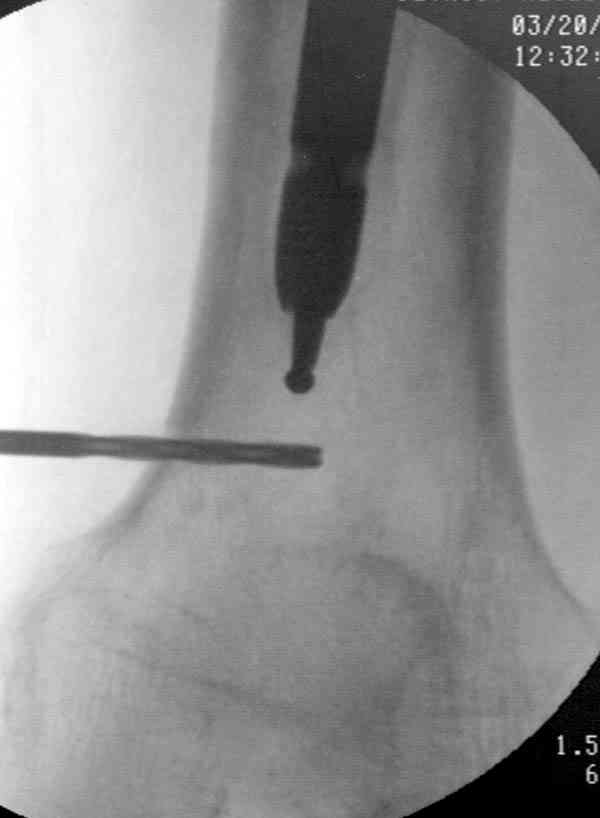

Приспособление для удаления сломанных штифтов и наличие ЭОП облегчит задачу. При отсутствии крючка тогда можно применить обычный длинный ball pointed guide wire от интрамедулярного набора. Проволока, пропущенная за пределы гвоздя и зажатая другая вытащат сломанный конец штифта без проблем.